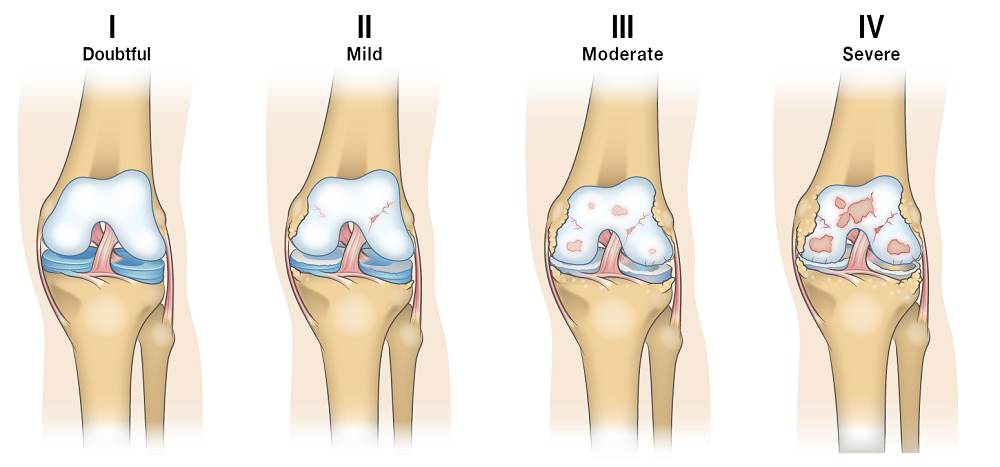

Ακτινογραφίες: Ο ακτινολογικός έλεγχος περιλαμβάνει και τα δύο γόνατα σε προσθιοπίσθιες και πλάγιες λήψεις. Ο έλεγχος γίνεται με τον ασθενή όρθιο έτσι ώστε να φορτίζει με το βάρος του τις αρθρώσεις του γόνατος.

Oι ακτινογραφίες αρχικά είναι σε θέση να μας δώσουν πληροφορίες για ασύμμετρη φόρτιση ή για πιθανές παραμορφώσεις (ραιβότητα, βλαισότητα). Στη συνέχεια ελέγχονται για στένωση του μεσάρθριου χώρου μεταξύ των οστών του μηρού και της κνήμης, σκλήρυνση του υποχόνδριου οστού και δημιουργία νέου οστού στις παρυφές της άρθρωσης (οστεόφυτα).